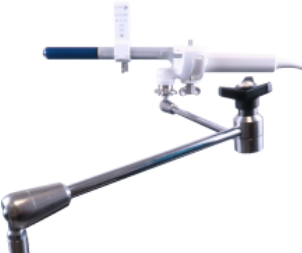

Transperineal

Procedures

KOELIS® offers a 3D side-fire ultrasound probe, probe holder and guides that improve visualization and during transperineal prostate biopsy.